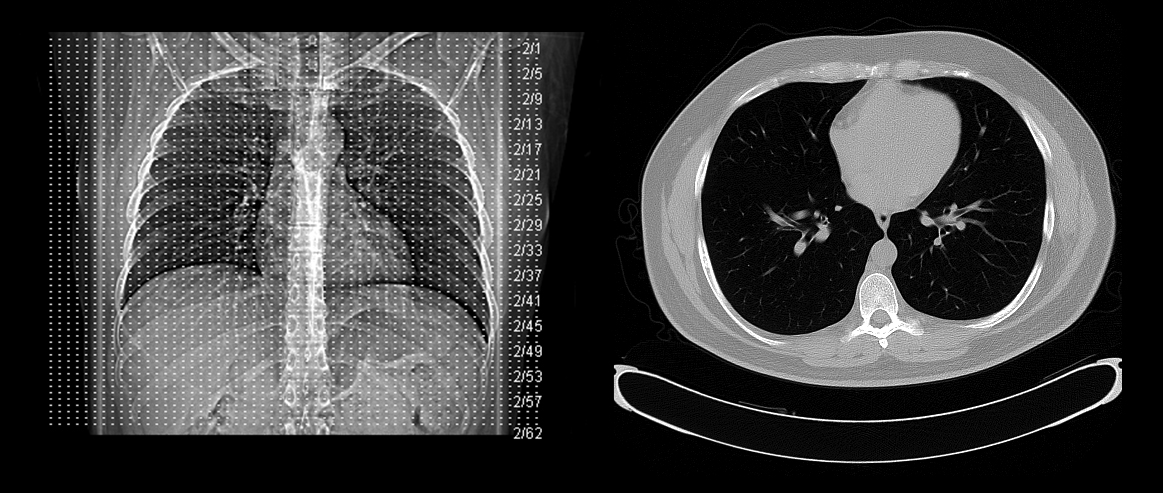

Standard adult chest phantom with lungs, heart, mediastinum, and ribs